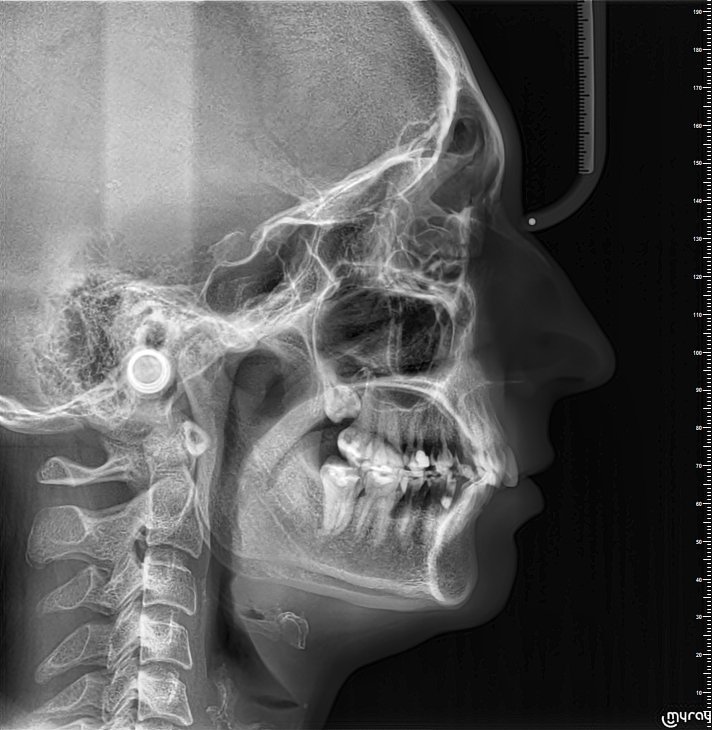

Здравейте, случайно при снимка по друг повод ми откриха ретиниран мъдрец. До този момент не съм имала оплаквания и не съм знаела за неговото съществуване. Може ли да ми кажете дали се налага да го извадя и евентуално крие ли рискове в бъдеще. Прилагам рентгенова снимка. Благодаря предварително.

По тези снимки не е възможно да се прецени в каква посока е мъдреца. Може да е пред или зад съседни зъб. Най-добре се вижда на СВСТ (3д рентген). Ако не ви създава проблеми и ако не притиска седмицата - по-добре не го пипайте.